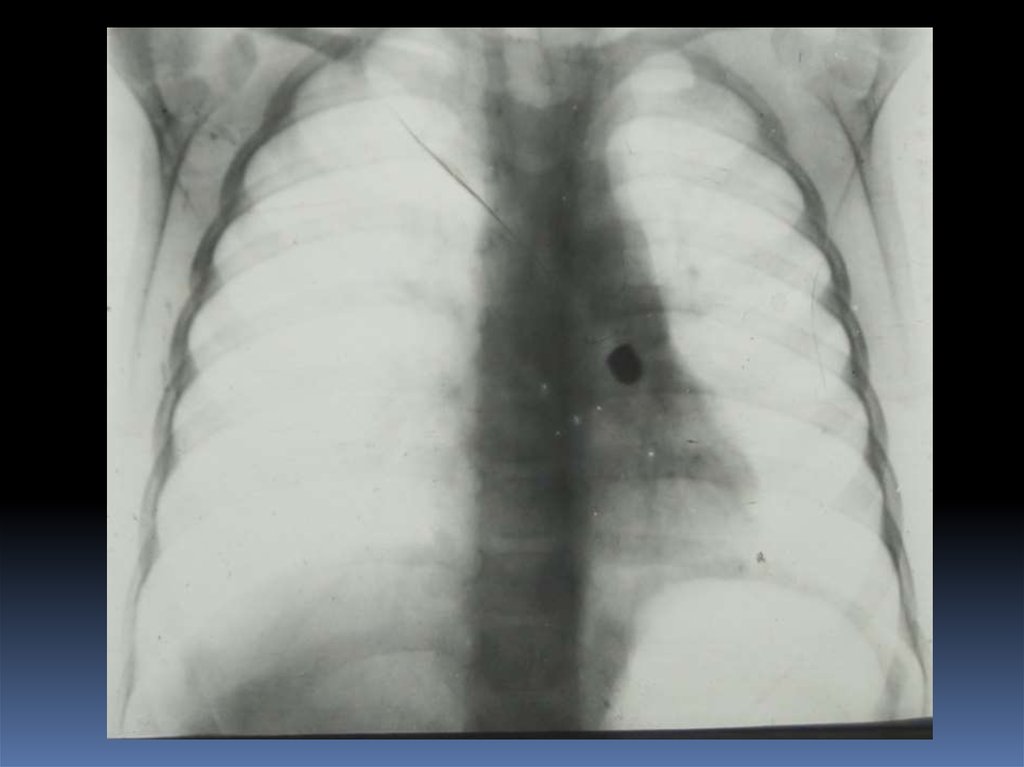

5. Проведение рентгеноскопического исследования раненого.

6. Проведение рентгенографического исследования раненого.

7. Виды травматического повреждения грудной клетки:

пневмоторакс;

гемоторакс;

гемопневмоторакс;

внутрилегочные гематомы;

дисковидные ателектазы;

посттравматические пневмонии.